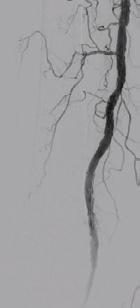

O altă complicaţie a diabetului zaharat asociată cu un grad semnificativ de morbiditate este boala arterială periferică, pacienţii diabetici prezentând mult mai precoce stenoze carotidiene semnificative sau ischemie cronică de membre inferioare complicată cu ulceraţii sau gangrenă care necesită o abordare multidisciplinară cu departamentele de chirurgie vasculară sau cardiologie intervenţională pentru salvarea membrelor. Oportunităţile de revascularizare sunt adesea reduse la pacienţii diabetici datorită leziunilor multiple și distale faţă de cazurile care nu asociază diabet. Investigaţiile bolii arteriale periferice cuprind indicele gleznă-braţ și haluce-braţ, ecografia Doppler și angiografia intervenţională, prin computer tomograf sau rezonanţă magnetică și calcularea scorului ’’WifI’’ pentru evaluarea riscului de amputaţie. Pe lângă soluţiile de revascularizare chirurgicală sau prin angioplastie percutană transluminală, pacienţii cu boală arterială periferică cronică simptomatică fără risc de sângerare înalt beneficiază de tratament cu Rivaroxaban în doză mică (2.5mg de 2 ori pe zi) și acid acetilsalicilic.